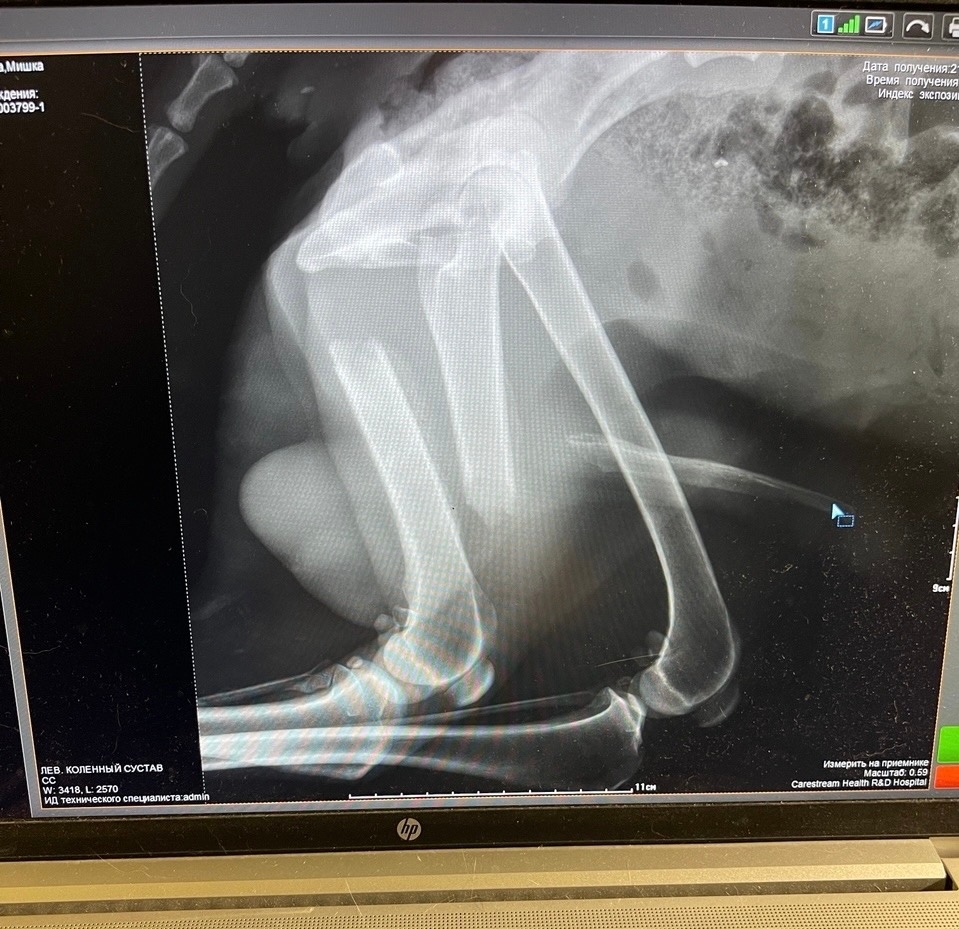

История Мишки такова: пёс безучастно лежал несколько дней на Пучковке, свернувшись калачиком. Сил ходить уже не было. Моя подруга детства [id237857644|Наталья Данилина], абсолютно неравнодушный человек и мама троих детей, имея на данный момент шесть своих собак, не смогла проехать мимо умирающего пса. Мишку повезли в ветклинику, сдали анализы и сделали рентген. Букет болезней полный: перелом задней лапы, ушибы всего тела, пироплазмоз, анемия, проблемы ЖКТ, обезвоживание.

Миша в клинике